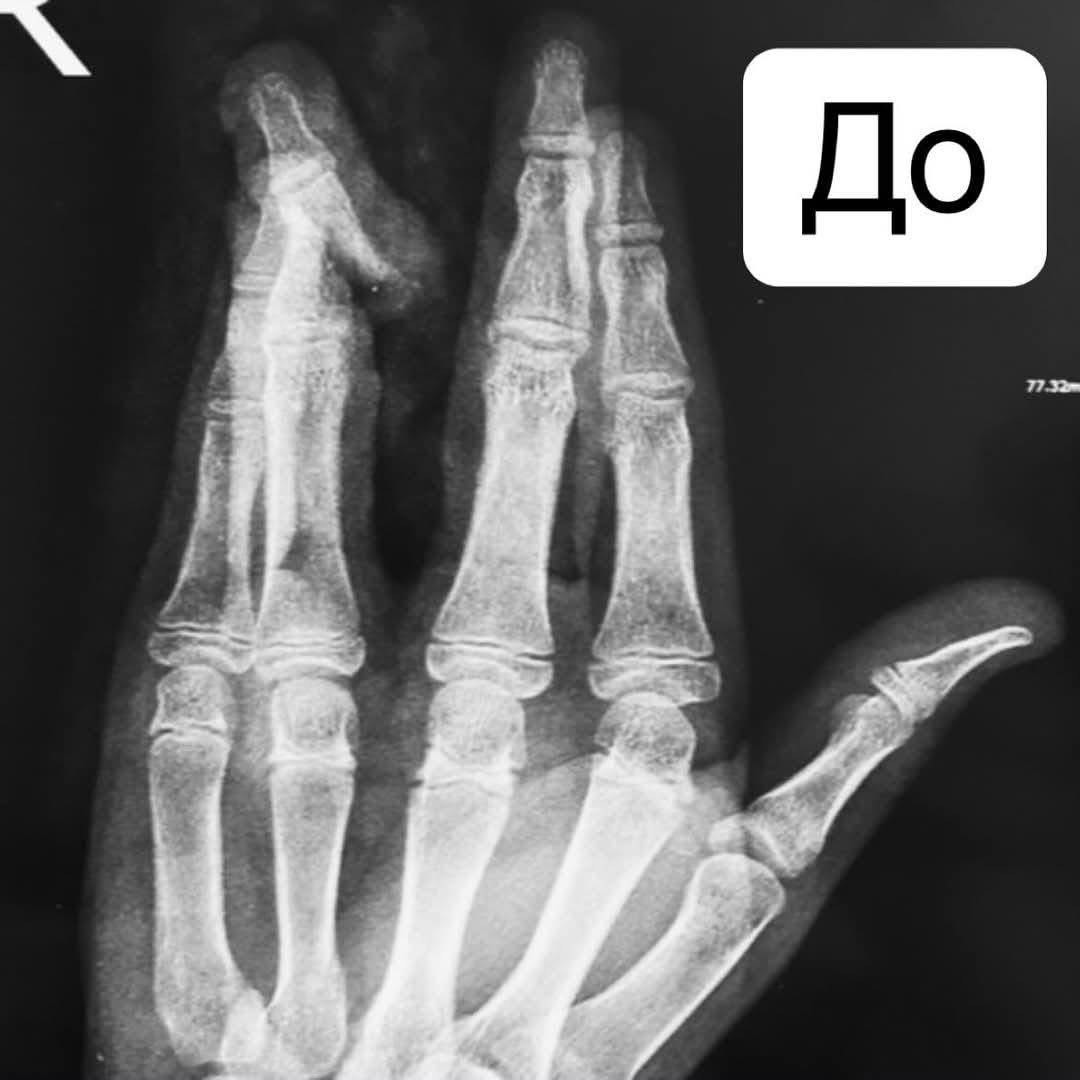

Днями до травматологічного пункту Вінницької обласної дитячої клінічної лікарні карета швидкої допомоги доставила 12-річний хлопчик із частковою травматичною ампутацією IV пальця правої кисті після падіння з самоката.

Діагноз медиків: повне пошкодження латеральних пучків сухожилка-розгинача та глибокого сухожилка-згинача пальця, відкритий перелом середньої фаланги IV-го пальця правої кисті зі зміщенням.

В умовах операційної лікарі виконали первинну хірургічну обробку рани, відкриту репозицію уламків середньої фаланги з фіксацією шпицею, пластику латеральних пучків сухожилка-розгинача, ушивання країв рани.

Через складність травми пластику глибокого сухожиллля лікарі вирішили провести в плановому порядку, аби максимально зберегти функцію пальця та уникнути ампутації.

Уже після першого етапу лікування була помітна позитивна динаміка: відновлене розгинання пальця, цілісність кістки та м’яких тканин, циркуляцію крові.

Після регенерації мʼяких тканин і зрощення кістки на дитину чекає наступний етап — пластика глибокого сухожилка-згинача.